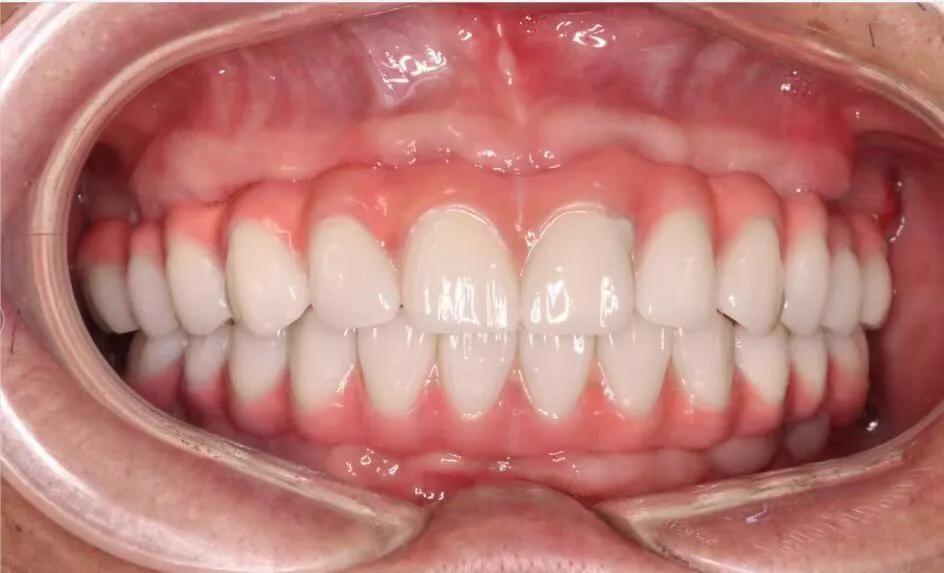

典型的負(fù)重,All-On-4。

這就是傳說中的當(dāng)天戴牙當(dāng)天吃飯,網(wǎng)上到處宣傳的就是這種種植方法。但是不是每一個(gè)人都能做這個(gè),All-on-4一般需要預(yù)約,醫(yī)生種植完畢,技師馬上開始取模做牙,大概5小時(shí)左右就可以戴上臨時(shí)牙回家吃飯了,休息一兩天,正常吃飯是沒問題的。